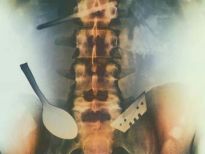

İki çatalı, bir tükenmez kalemi ve diş fırçasını yutmuş bir hasta.